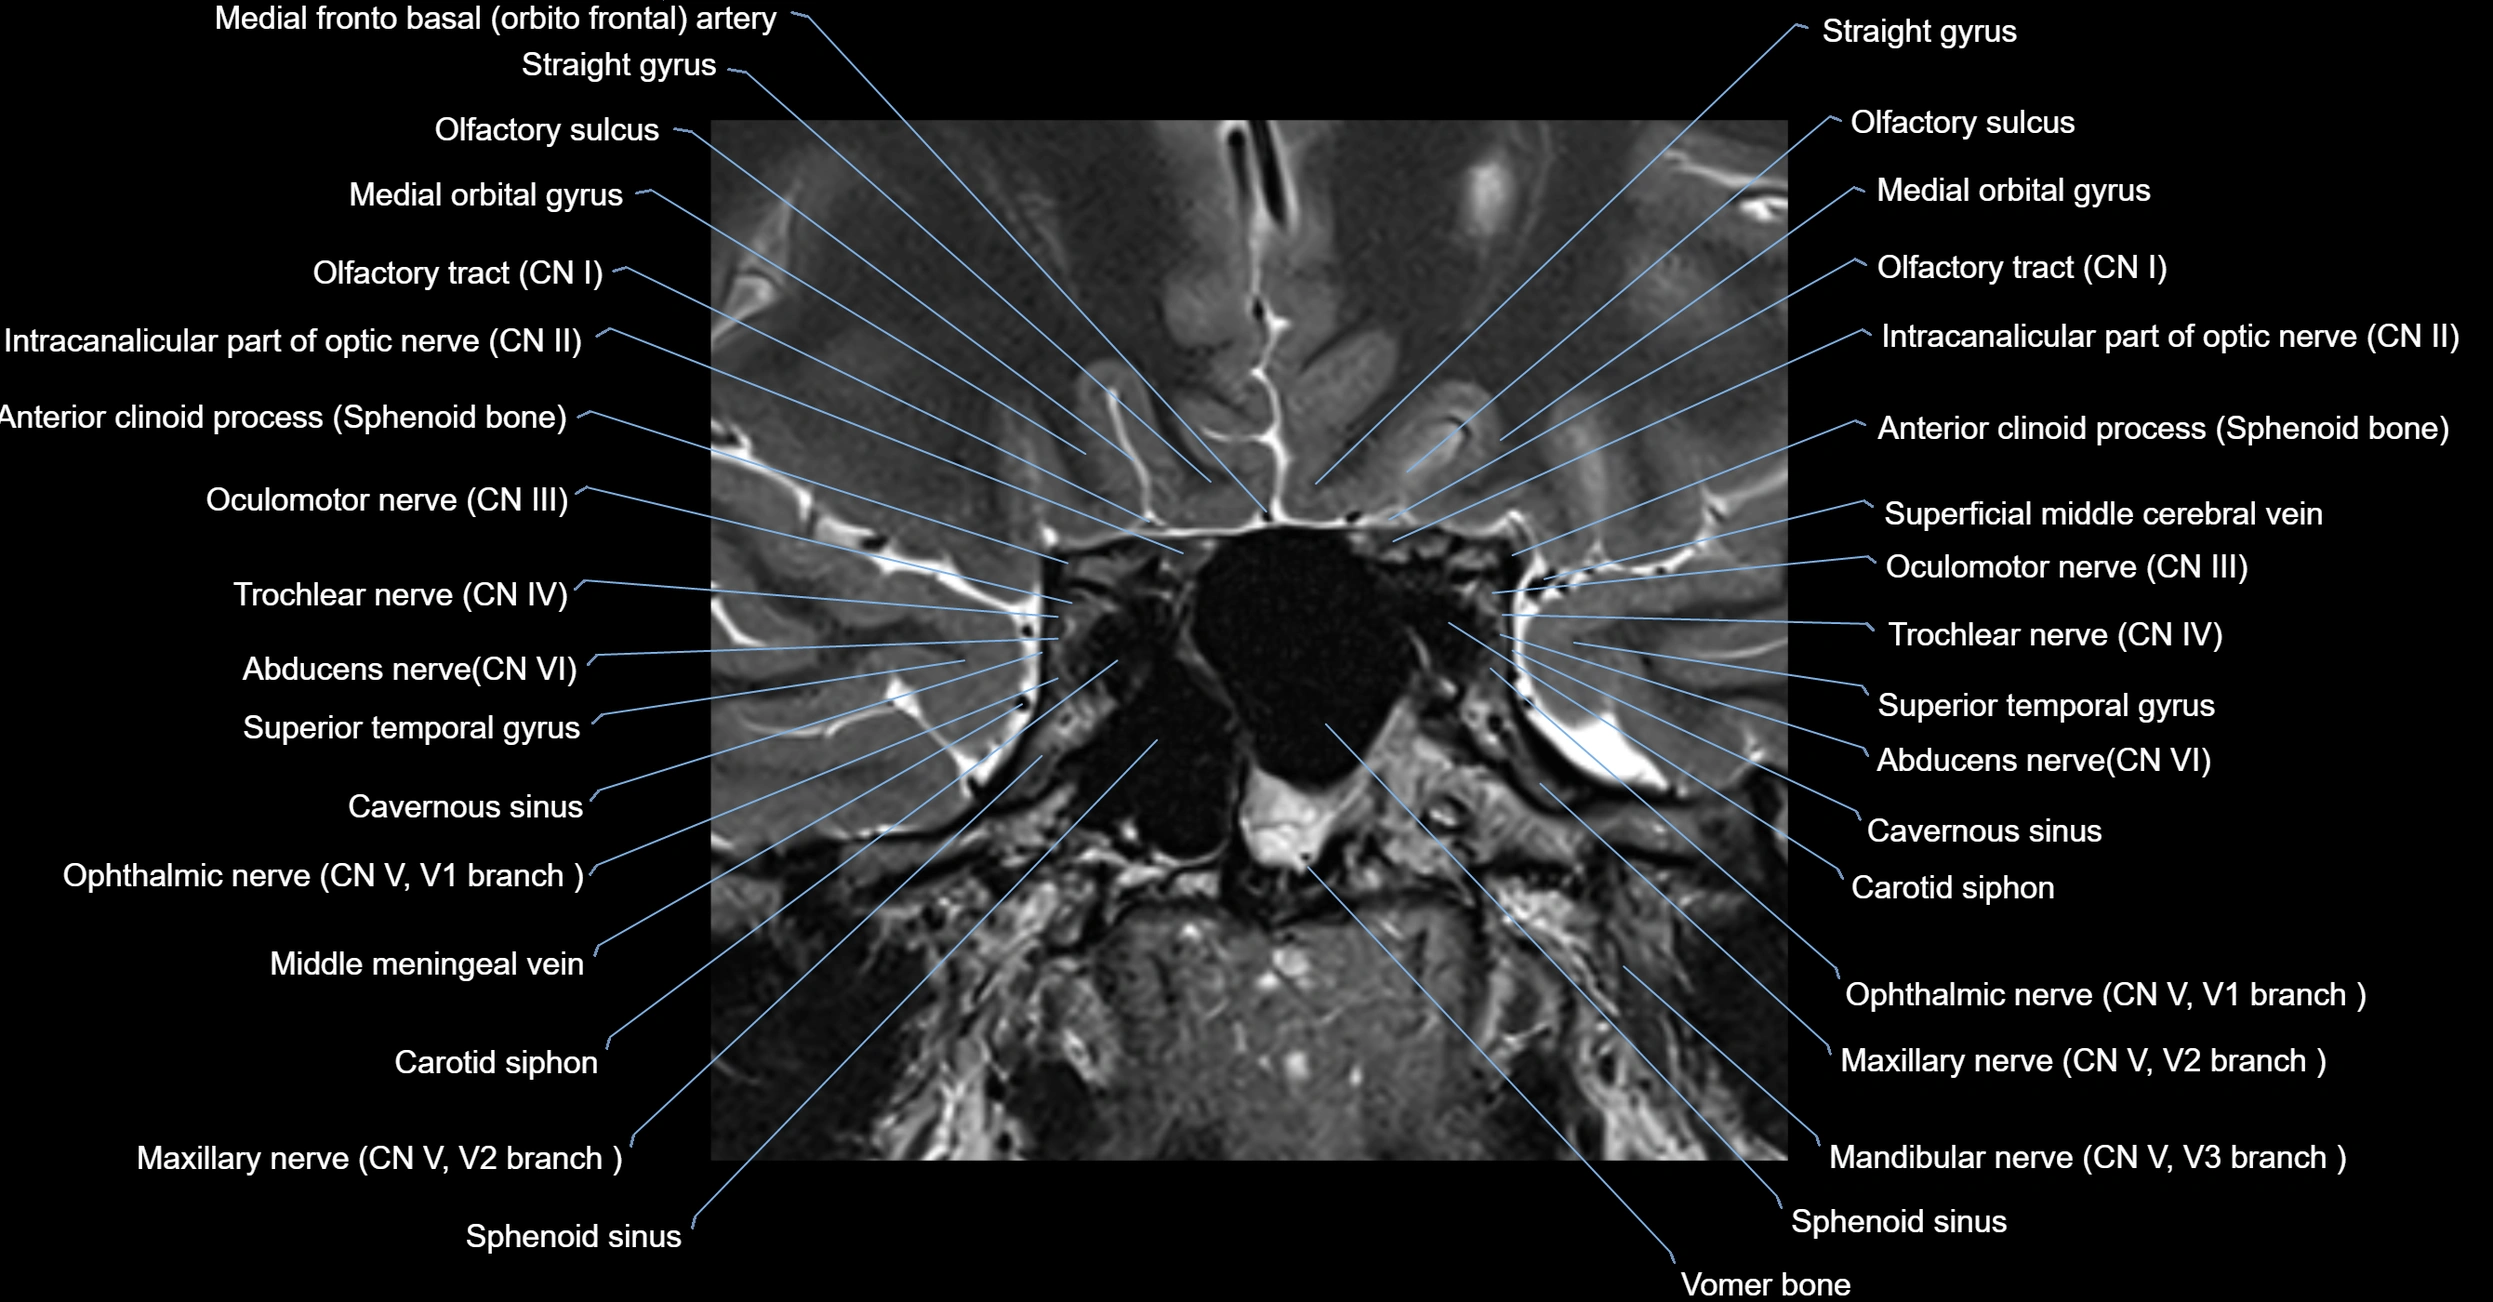

MRI images